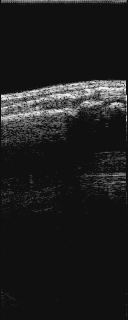

長軸像(画像の中で、左が中枢、右が末梢)

@患側            A健側          B患側           C健側

@は、患側の橈骨下端部に、背側より長軸にプロ−ブをあてた。

Aは、健側に、同様にプロ−ブをあてた。

これにより、橈骨末梢片が背側転位しているのがわかる。

Bは、患側の側方(橈側)より長軸にプロ−ブをあてた。

Cは、健側に、同様にプロ−ブをあてた。

これにより、橈骨末梢片が橈側転位しているのがわかる。